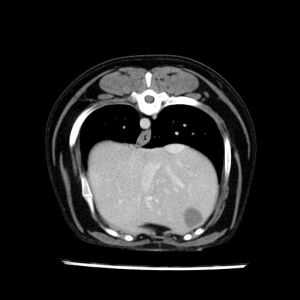

La lesione focale epatica , la ceus,la Tac e il chirurgo .